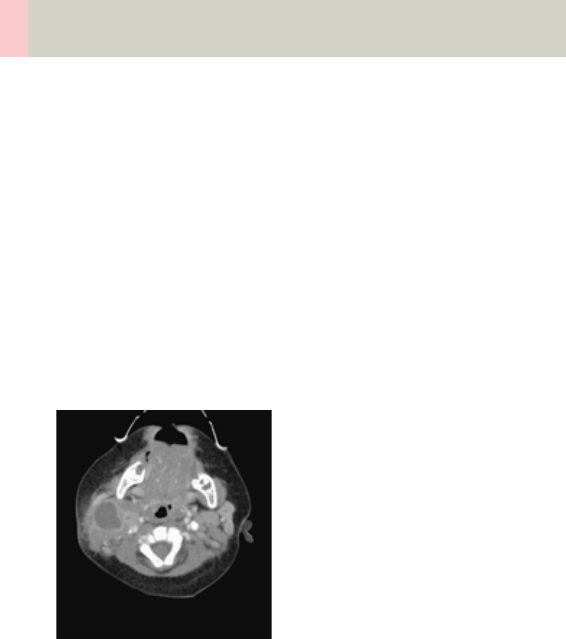

- NeckRoutine

Neck 204

•Overview 204

- General Hints 206

- Body Kernels 207

•Scan Protocols 208

- NeckRoutine 208

- NeckThinSlice 212

- NeckVol 214